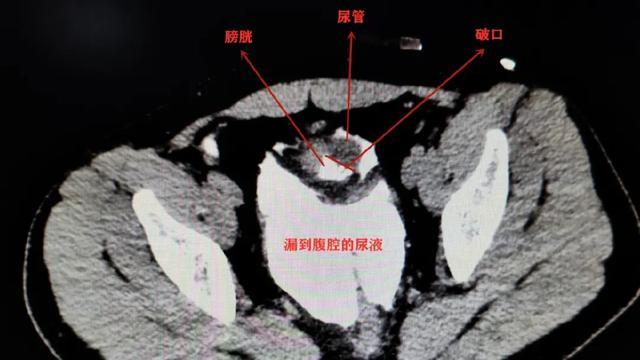

“如果再不及时手术 , 可能生命都会受到威胁 。 ”成都市第三人民医院泌尿外科副主任医师袁仁斌博士告诉采访人员 , 当时 , 小李膀胱有一个4*3cm的破洞 , 尿管顺着洞“跑”到了腹腔内 。 因为尿液在腹腔内蓄积了很长时间 , 已经引发了比较严重的腹膜感染 。

膀胱很容易外力撞破吗?袁仁斌说 , 尿量过多导致膀胱过度充盈 , 撞击的外力才会“有机会”对充盈的膀胱造成直接的作用 , “如果能及时排尿 , 也许就不会引起这次伤害了 。 ”